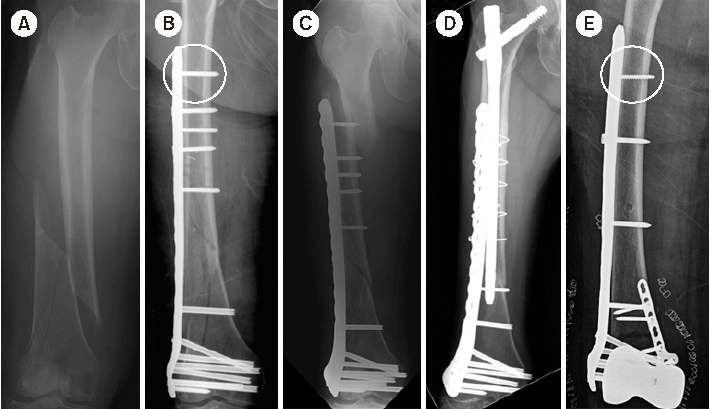

Fig. 6

(A) Radiograph of a distal femur fracture of a 74-year-old female after a ground-level fall. (B) Postoperative radiograph after a closed reduction and minimally invasive locked plating. (C) Six-week postoperative radiograph showing a stress riser fracture around the outermost locking screw after slip-down injury. (D) Radiograph showing bony union two years after overlapping intramedullary nailing. (E) Postoperative radiograph showing locked plating using a conventional cortical screw instead of a locking screw as a proximal outermost screw to minimize the stress riser.